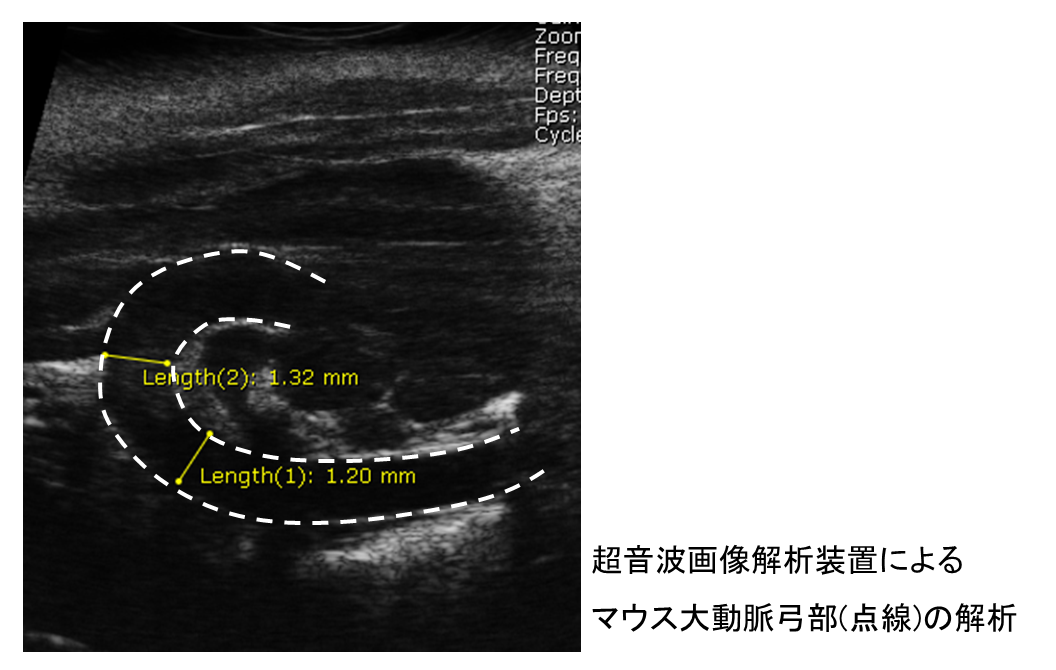

1つ目は「大動脈解離」に関する研究です。大動脈解離とは、大動脈の壁が裂けることで、もともとの血流が通る「真腔」と、新たにできた「偽腔」という空間が形成される疾患です。日本では主に70代に多く発生し、急激に進行するうえに死亡率も高いため、発症時には迅速な診断と治療が非常に重要です。しかし現在のところ、発症を未然に防ぐ有効な手立ては確立されていません。もし、発症の予兆を捉え、解離自体を予防できるようになれば、この疾患克服への大きな一歩となるでしょう。そこで私は、大動脈解離を誘発するモデルマウスを用い、発症の前後における病態メカニズムの解明を目指しています。そして将来的には、診断や予防に役立つツールの開発を目指しています。